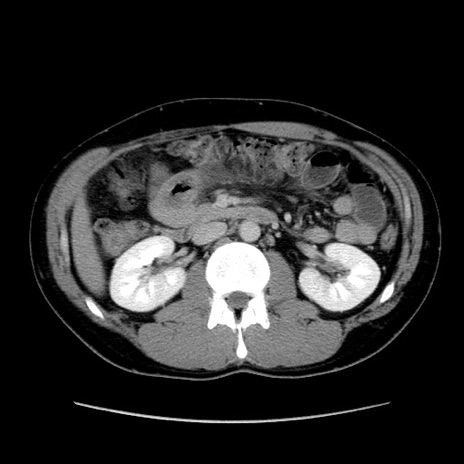

症例36(横断像)

【症例】20歳代 男性

【主訴】心窩部痛

【現病歴】今朝より上腹部痛あり。一旦軽快していたが再度出現したため救急要請。昨日夕に白身の魚を含む刺身を食べた。

【身体所見】BP 136/89mmHg、HR 74/min、BT 37.0℃、腹部:膨満、軟、心窩部に圧痛あり。反跳痛なし、筋性防御なし、腸雑音やや亢進あり。

【データ】WBC 17700、CRP 0.48